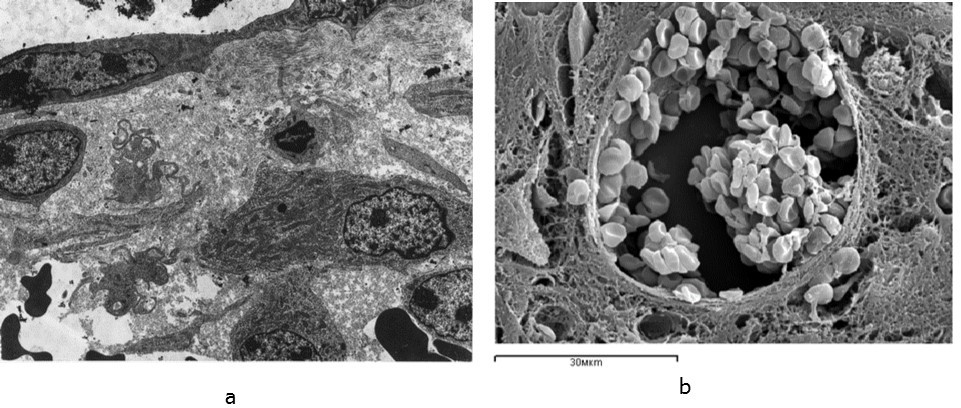

Electron microscopic examination in the area of the bone fragments revealed the foci of alternatively destructive changes and the areas of organized hematoma, infiltrated lymphocytes, neutrophilic granulocytes, monocytes, mast cells, macrophages (Figure 2a, 2b). Bone debris, filaments, fibers and clots of fibrin were revealed in the intermediate and endosteal zones of the regenerated bone; little-differentiated connective tissue with edema signs was formed. Isolated sinusoids with moderate ectasia, parietal micro thrombi, diapedesis of erythrocytes and leukocytes were observed in the regenerated bone. Perivascular cells were sporadic.

Figure 2.The ultrastructure of the intermediary zone of regeneration 7 days after the operation in the animals of the control group: a – transmission electron microscopy, b – scanning electron microscopy. Increase: a – 6000, b – 2000

The ultrastructure of the intermediary zone of regeneration 7 days after the operation in the animals of the control group: a – transmission electron microscopy, b – scanning electron microscopy. Increase: a – 6000, b – 2000